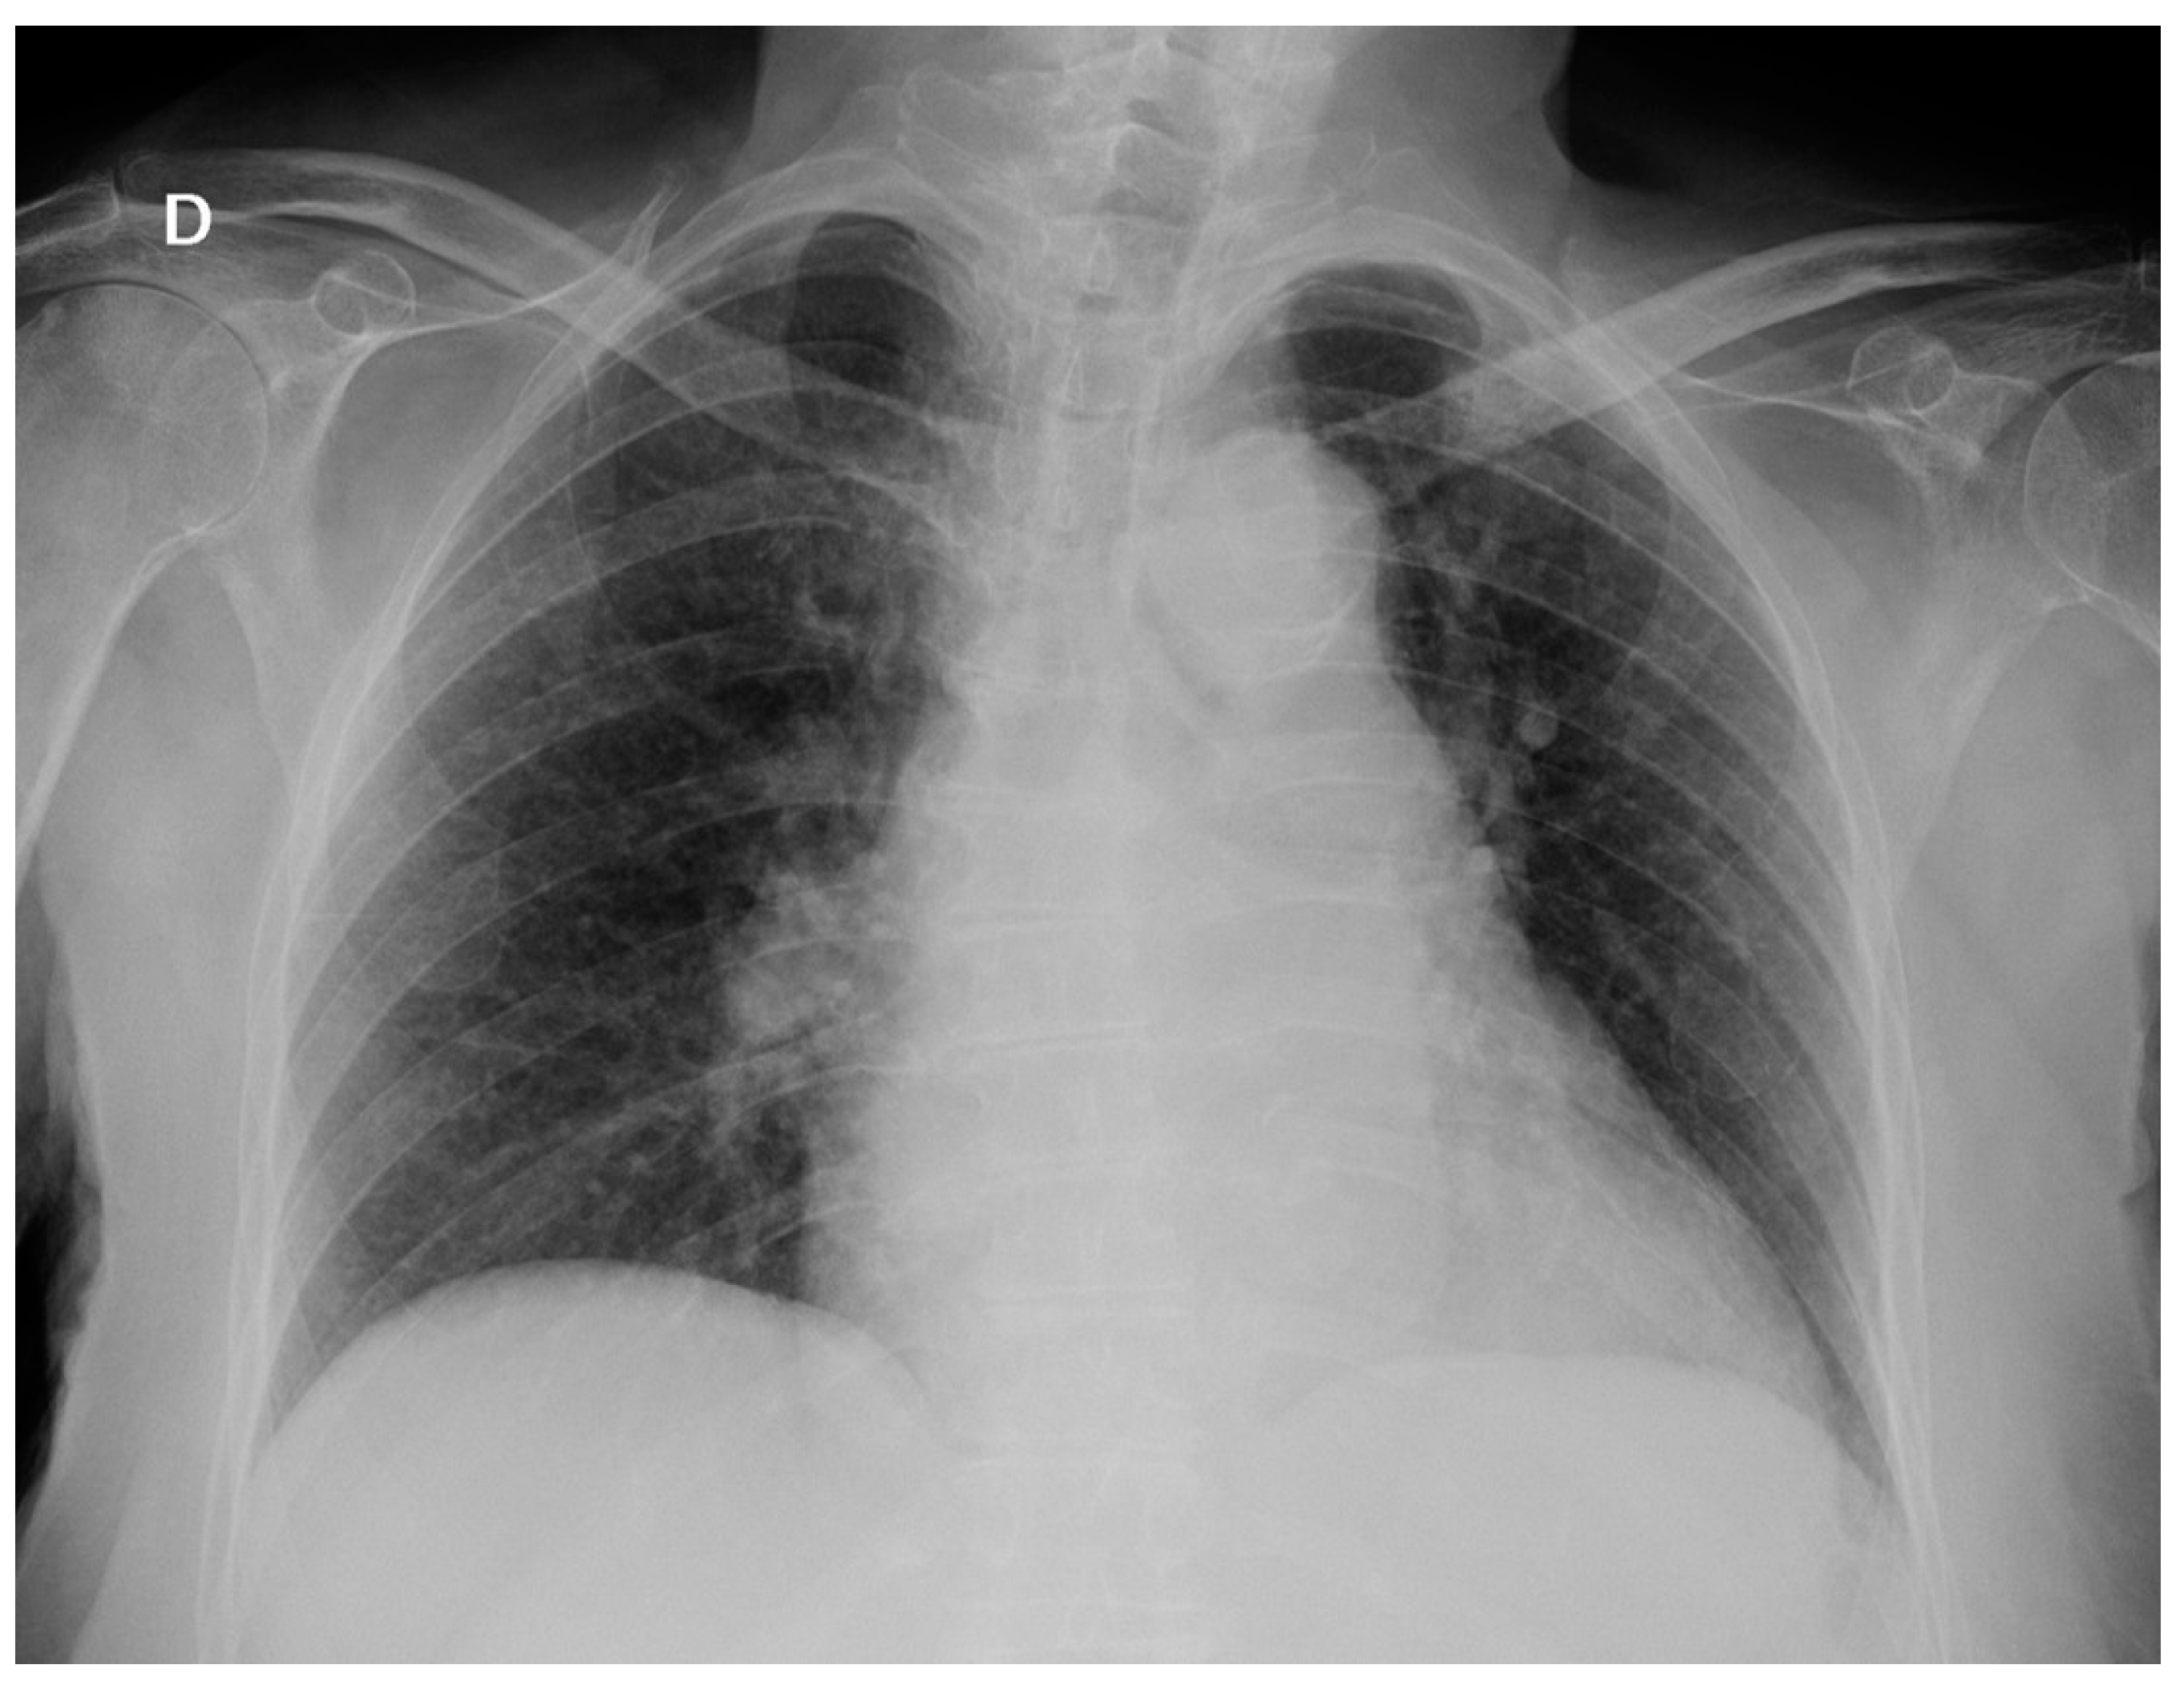

Three days later, the patient started with progressive dyspnea with productive cough. Arterial blood gas analysis showed PO2: 67 mmHg, PCO2: 39 mmHg and SatO2: 94% and a new chest X-ray (Figure 2) presented bilateral interstitial infiltrate. Sputum culture and acid-fast stain were negative. Urinary Legionella antigen was also negative.

Figure 2.

Chest X-ray on 7th day: Bilateral interstitial infiltrates.